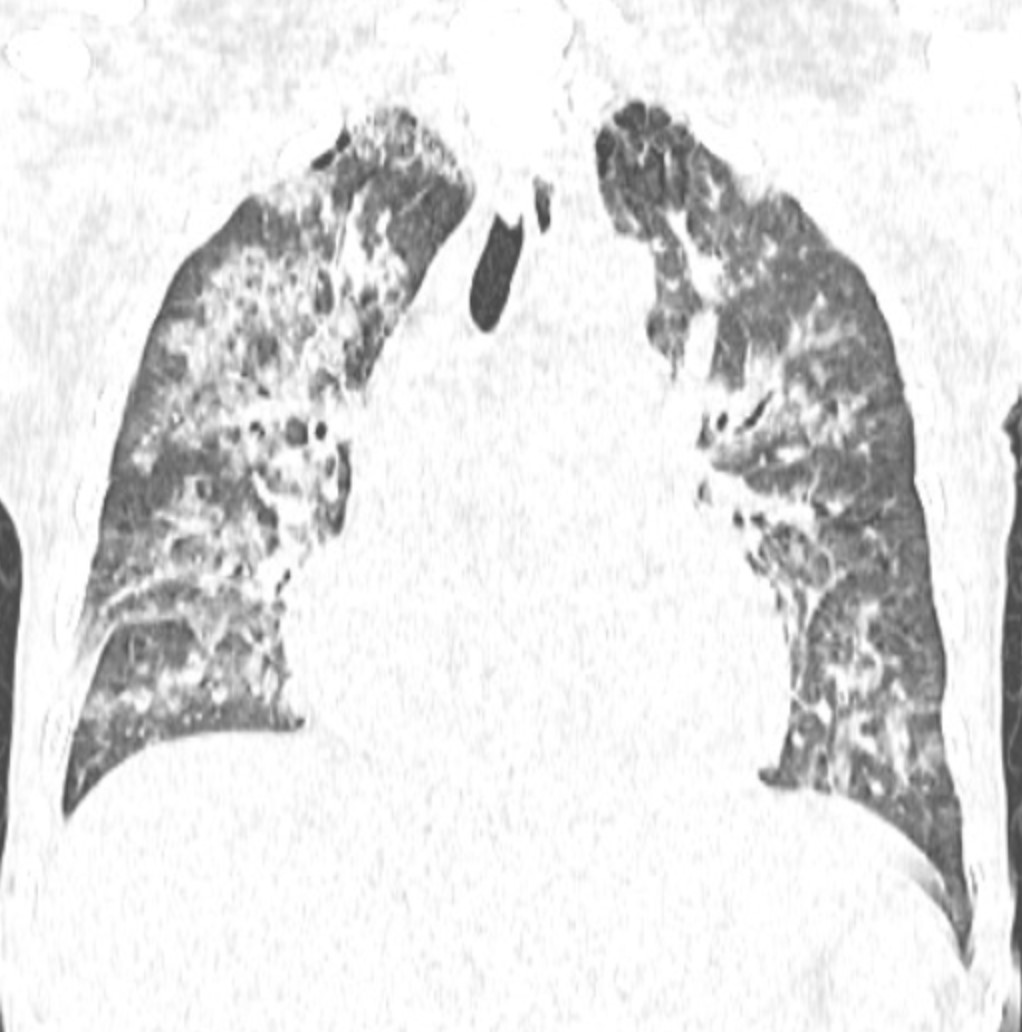

Đến ngày 24/10, trong một lần truyền huyết tương tiếp theo để xử lý tình trạng đông máu, người bệnh xuất hiện khó thở tăng dần chỉ sau khoảng 15-20 phút truyền, SpO từ 97% còn khoảng 88-90%, huyết áp tăng, tĩnh mạch cổ nổi, nghe phổi có ran ẩm hai bên.

Chụp CT scan phổi thấy hình ảnh phù phổi cấp, các xét nghiệm khác phù hợp với chẩn đoán Quá tải tuần hoàn liên quan tới truyền máu (TACO). Kíp trực đã dừng truyền, cho thở oxy, đặt tư thế ngồi và dùng thuốc lợi tiểu, nên người bệnh cải thiện triệu chứng.

Ảnh: Phim chụp Xquang phổi của bệnh nhân C.Đ.C (21/10) và CT scan (24/10)